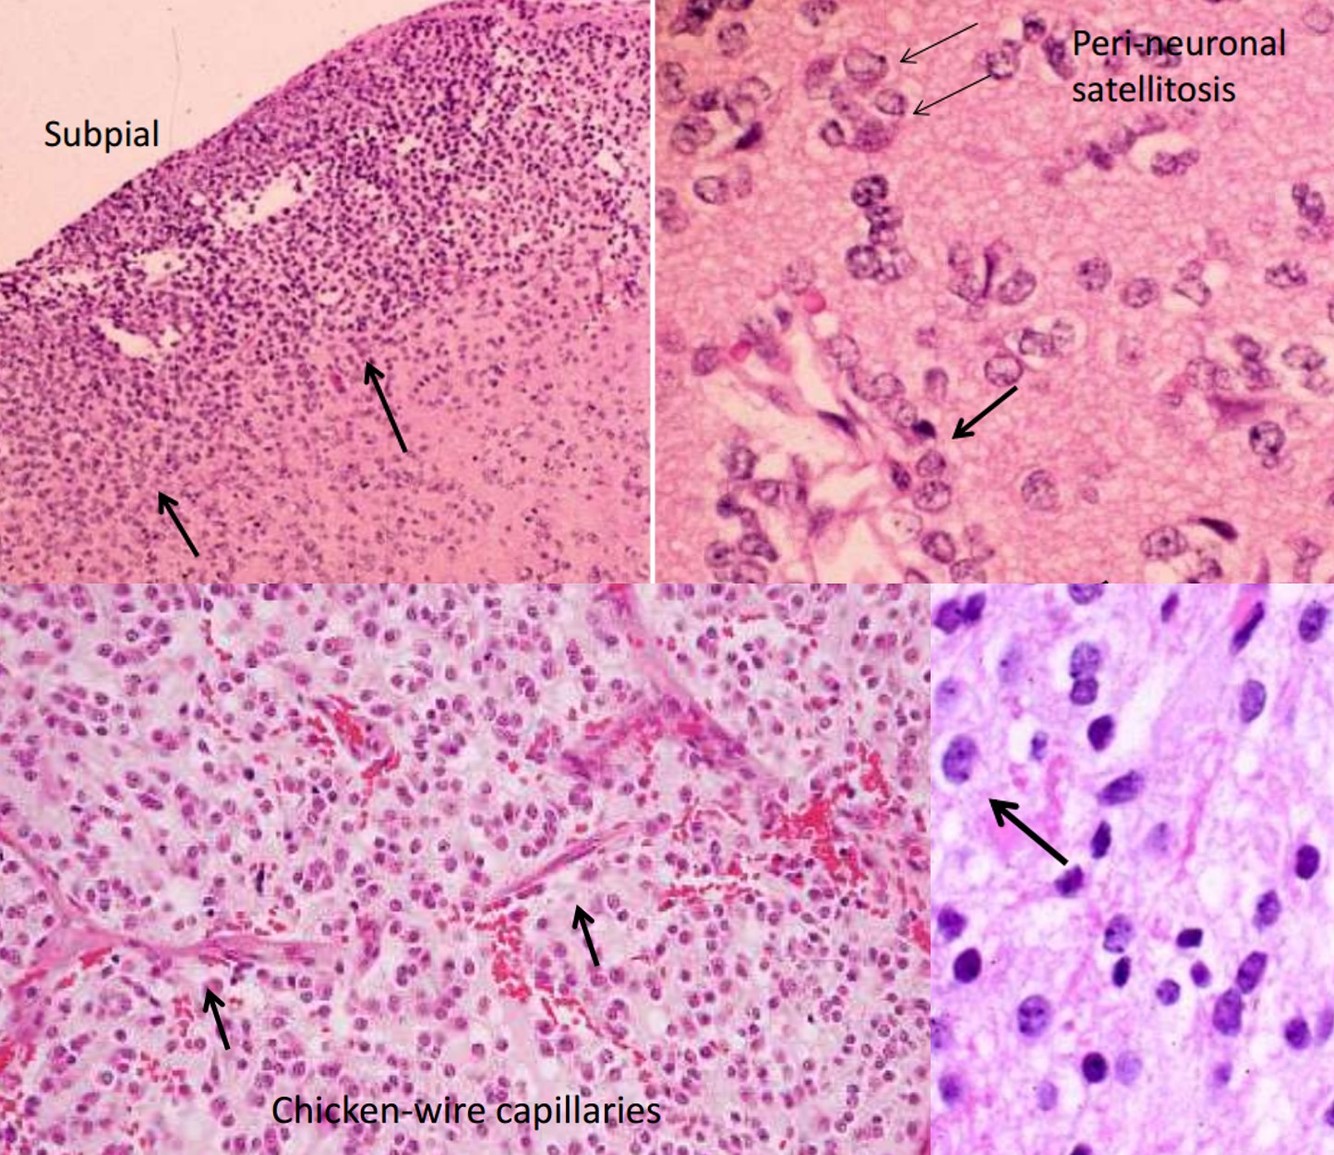

Oligodendroglioma

- 5-15% of gliomas

- Age: 40 ~ 50 y/o, rare in children

- Restricted to supratentorial compartment

- Interval to anaplastic progression is longer relative to astrocytoma (range 9y, vs 4-5y for latter)

- 1p, 19q deletion, oligodendroglial ‘signature’; connotes chemosensitivity